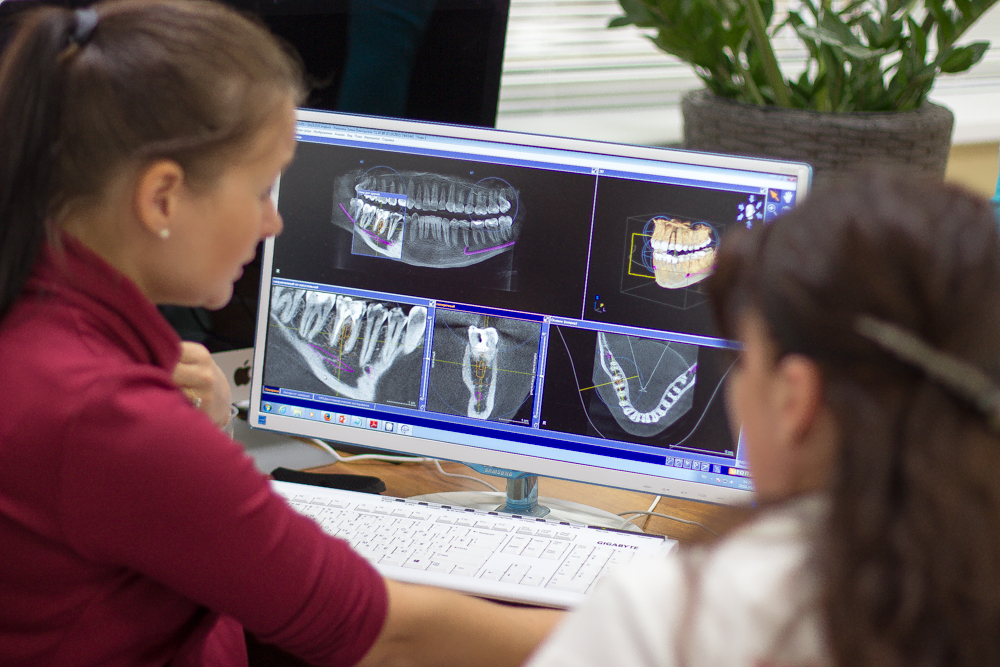

Фотографии и изображения КТ аппарата ORTHOPHOS SL

Раздел: Мудрость в фокусе